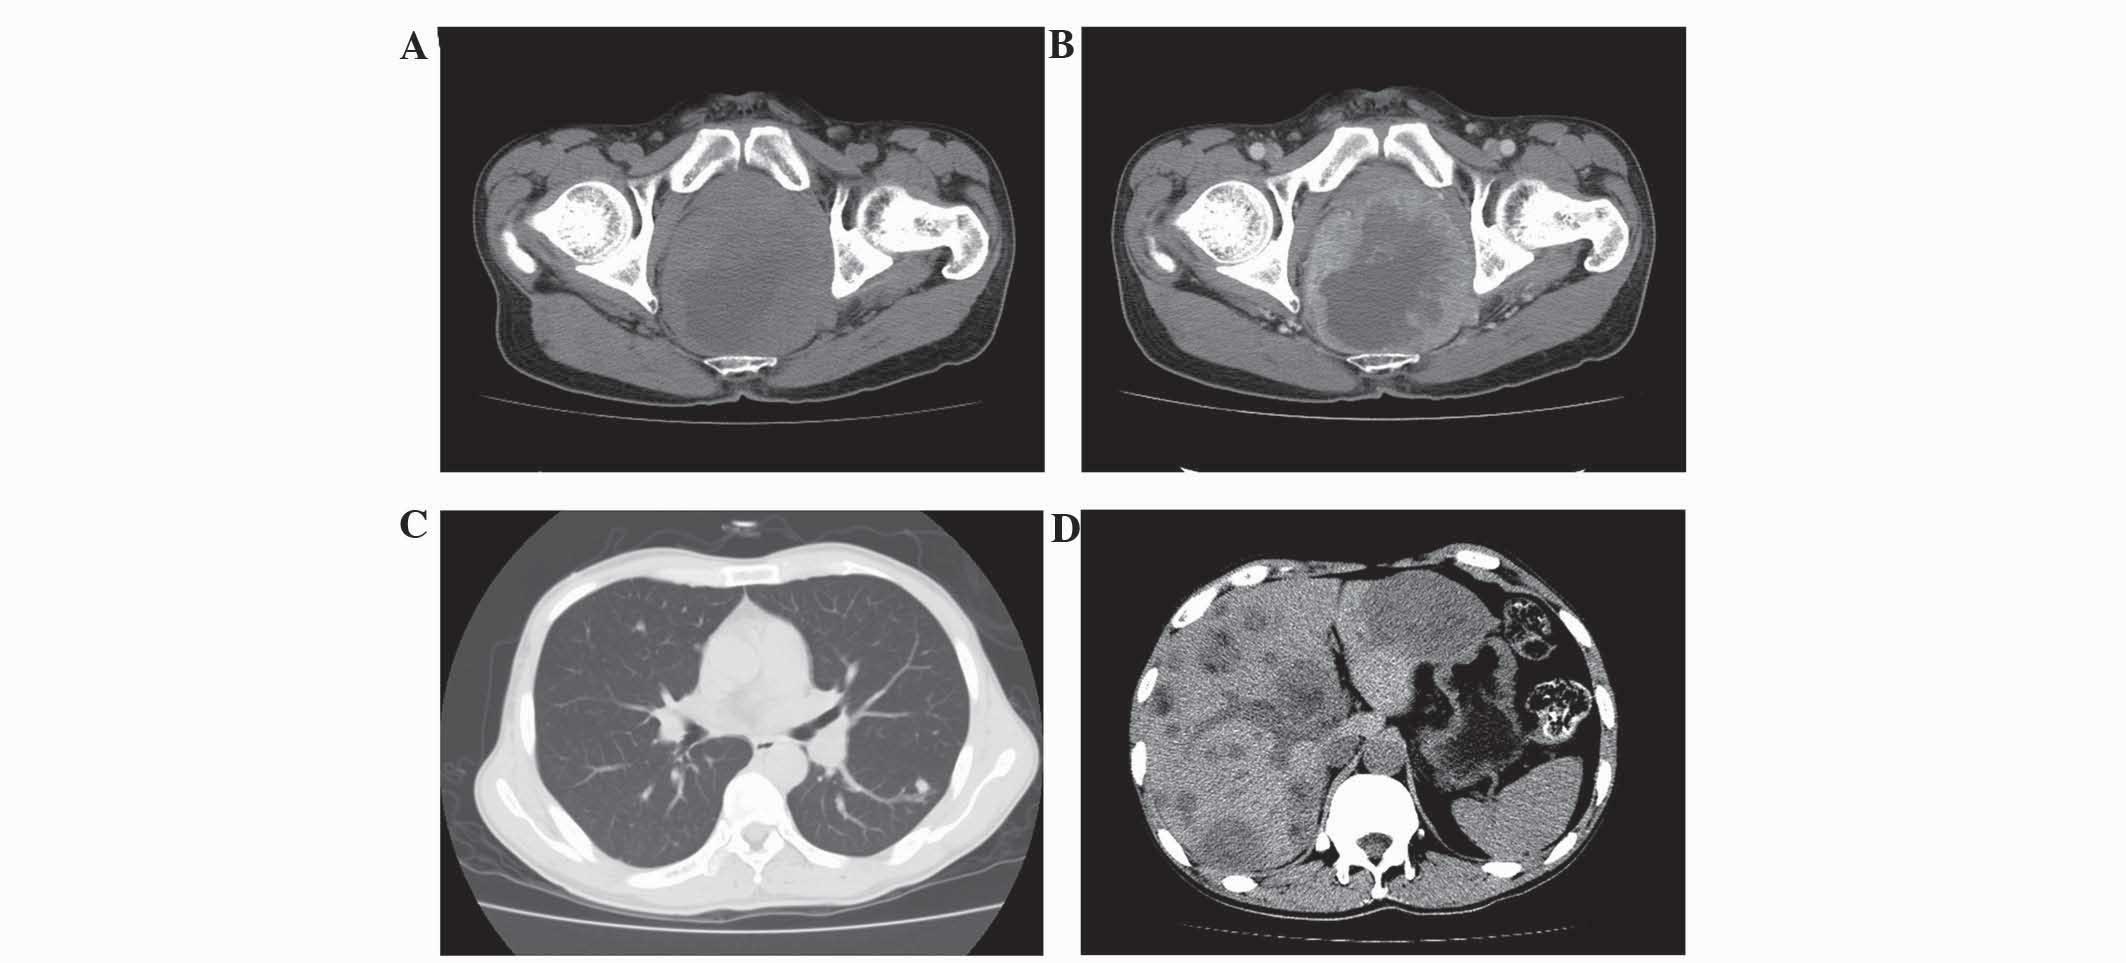

The CT and MRI results are summarized in Table I. All 4 patients exhibited ring-like rectal wall thickening, hypodensity compared with the gluteus muscles on non-enhanced CT images, isointensity on T1WI and hyperintensity on T2WI. Thickening of the left wall of the rectum with patchy low attenuation and the presence of an exophytic mass was observed in 1 patient (patient 4; Fig. 1). Local tumor invasion of the perirectal fat spaces was observed in 4 patients. Tumor invasion of the seminal vesicle was exhibited by 1 patient (patient 1), and tumor invasion of the seminal vesicle and prostate gland was exhibited by 1 patient (patient 4). Heterogeneous attenuation was found on non-enhanced CT images in 3 lesions (patients 1, 2 and 4), and 1 lesion exhibited heterogeneous intensity on non-enhanced MRI (patient 3). All the lesions demonstrated strong enhancement following contrast imaging. Lymphadenopathy was observed in 4 patients, pulmonary metastasis in 2 patients (patients 3 and 4), liver metastasis in 3 patients (patient 2–4) and multiple bone metastases in 1 patient (patient 3; Fig. 2).

Figure 1.

CT scans of a 45-year-old man with small cell carcinoma of the rectum (patient 4). (A) Axial non-enhanced CT scan demonstrating a thickened left wall of the rectum, with patchy low attenuation and the presence of an exophytic mass. Tumor invasion of the prostate glands and seminal vesicle was also observed. (B) Axial contrast-enhanced CT scan demonstrating heterogeneous strong enhancement. (C) Axial CT scan demonstrating the presence of multiple lung metastases. (D) Axial non-enhanced and contrast-enhanced CT scan demonstrating the presence of multiple liver metastases. CT, computed tomography.